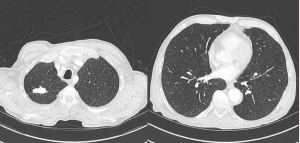

BCG-ite : un cas de granulomatose systémique

Cas clinique Contexte M. P., 71 ans est hospitalisé en médecine interne pour un syndrome confusionnel fin octobre 2021. Il a pour antécédents une thalassémie, une polyarthrite rhumatoïde non traitée,…